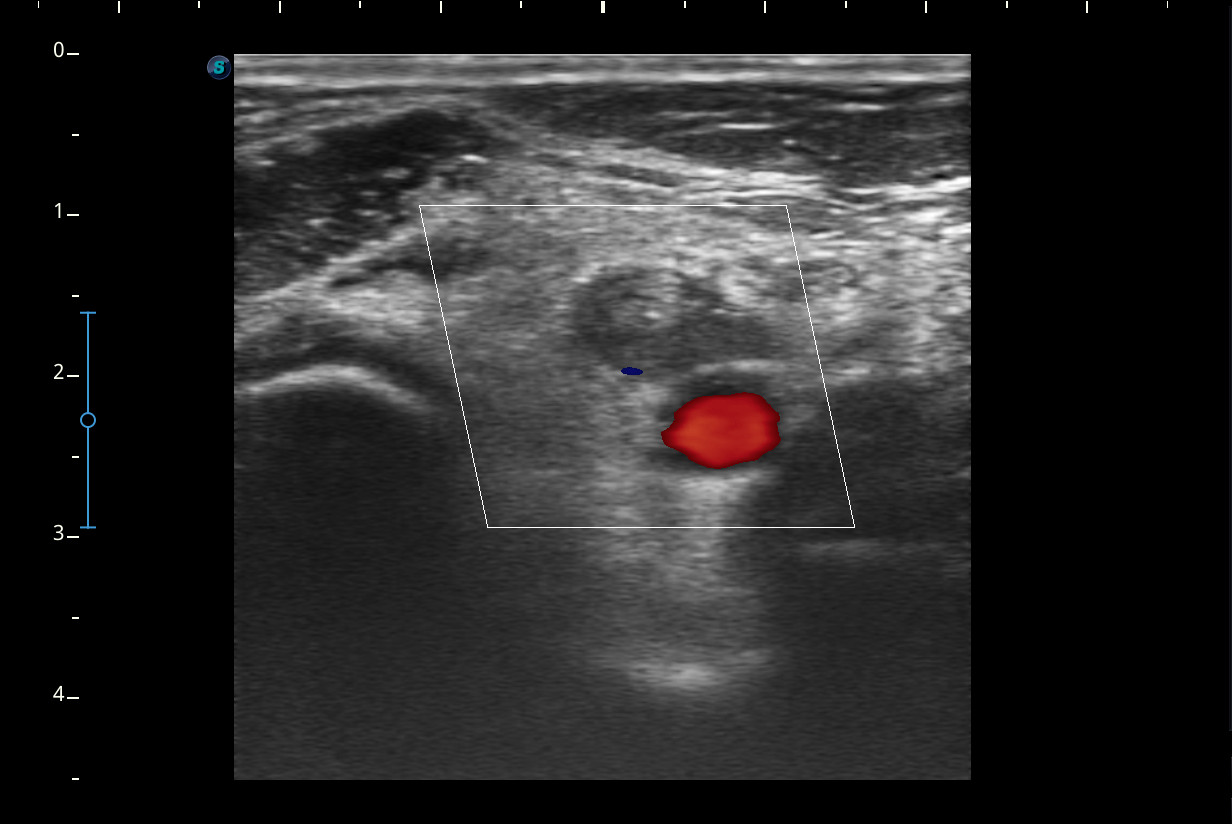

Se realiza ecografía del Miembro inferior derecho.

A nivel del hueco poplíteo se visualiza presencia de trombosis de la vena poplítea, no así en localizaciones proximales.